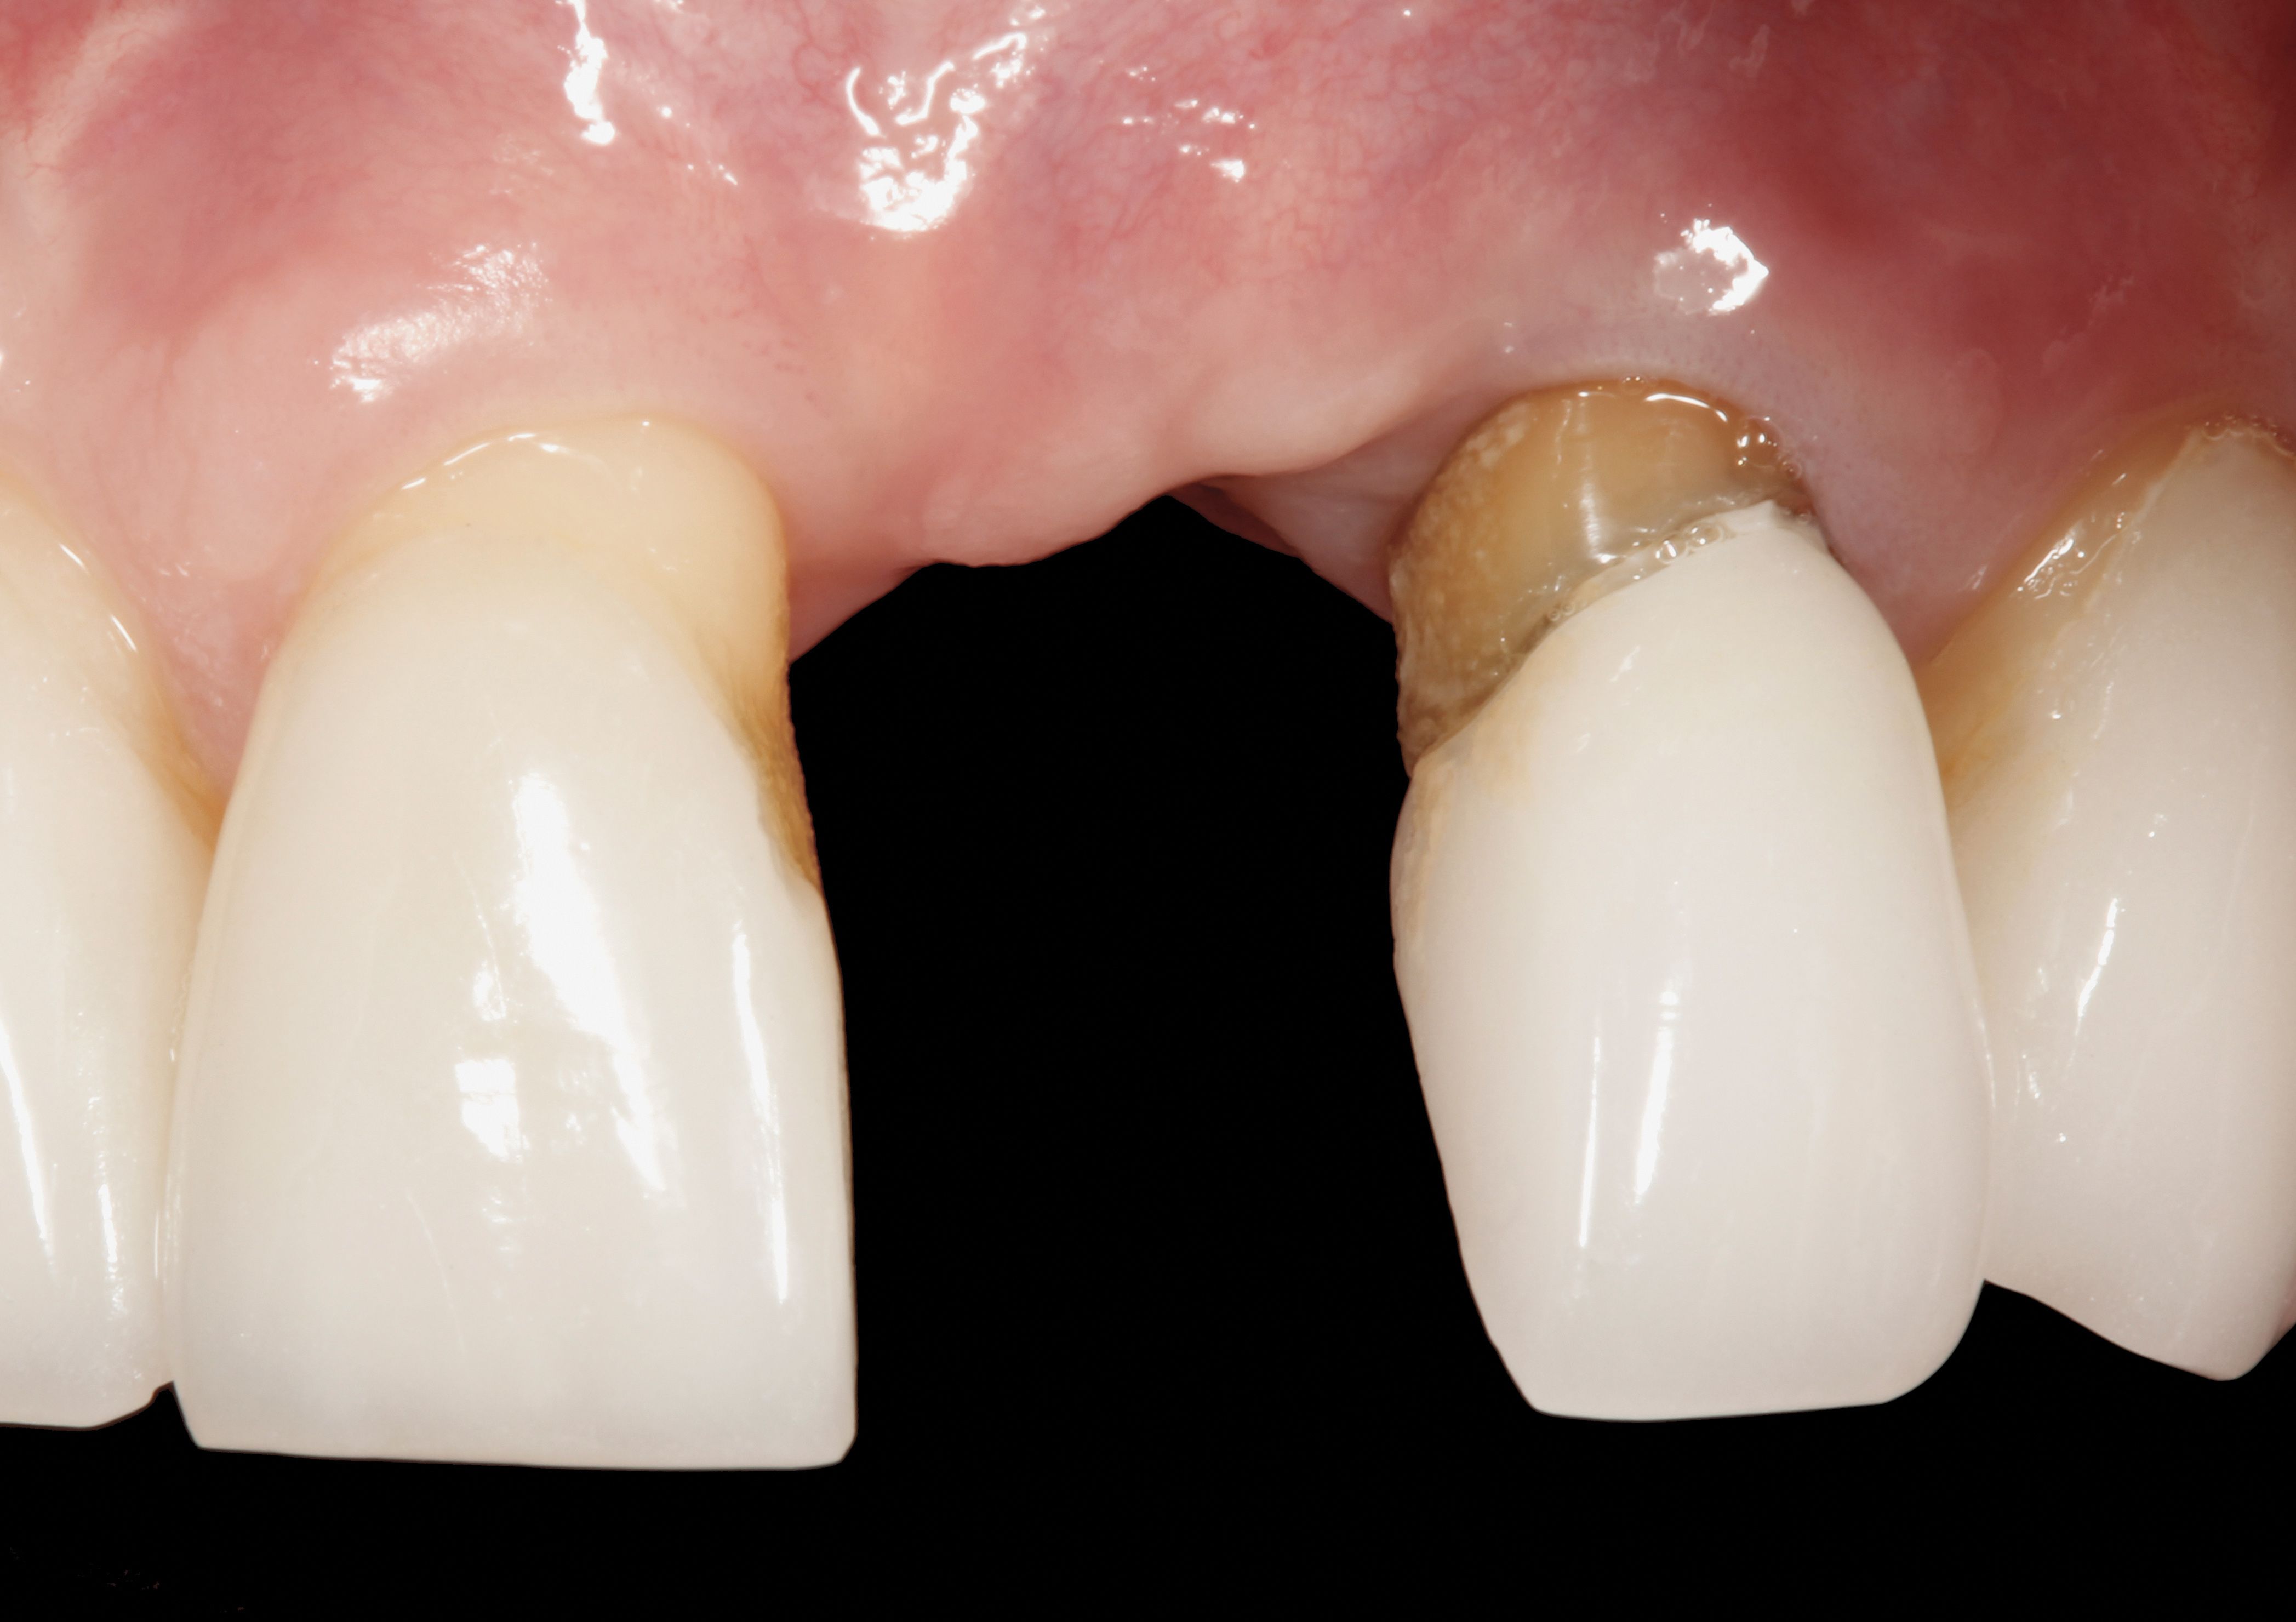

The following case report provides an example of this case scenario: A 24-year-old white male presented with congenitally missing tooth No. 26 restored with a single-tooth cement-retained implant restoration. The implant was placed excessively to the facial aspect of the edentulous site and too shallow, and the periodontal phenotype was thin scalloped (Figure 32). In an effort to mimic the lost midfacial soft tissues, pink ceramics were used as a cosmetic facade. Even though the restoration was not in the esthetic zone, the patient was highly displeased with the esthetic outcome and sought remediation.

The crown and screw-retained custom abutment were removed, and a surgical cover screw was placed into the implant, thereby allowing spontaneous gingival augmentation in situ (Figure 33 and Figure 34). Note that the lingual aspect of the implant site was significantly more coronal than the labial aspect, which was positive because the defect would be limited to a facial–lingual defect. A fixed RBR bridge was cemented on the adjacent teeth and used as a tooth-supported transitional provisional restoration (Figure 35). A few weeks were allotted to let the soft tissue heal and migrate around the cover screw (Figure 36) to see if there would be complete coverage, thereby allowing a soft-tissue augmentation procedure to be performed with primary flap closure as in clinical scenario No. 2. The major obstacle in achieving a positive tissue response was that the implant depth was also deficient because the implant–abutment connection was at the level of the free gingival margin. It was decided that the best treatment option would be to remove the implant. A high-powered reverse-torque device (Fixture Remover Kit, NeoBiotech, www.neobiotechus.com) was used to remove the implant atraumatically (Figure 38 through Figure 41). The implant socket was allowed to heal for several months not unlike an extracted tooth (Figure 42). A new implant was placed in a better position from both a restorative and esthetic perspective (Figure 43), and after a few months of healing, a new crown was made (Figure 44). A satisfactory functional and esthetic result was achieved (Figure 45 and Figure 46) without employing pink porcelain.

Fig 32. A dissatisfied patient presented with significant midfacial recession of implant restoration of tooth No. 26. Pink ceramic material was used unsuccessfully to prosthodontically compensate for the lost midfacial tissue.

Figure 32